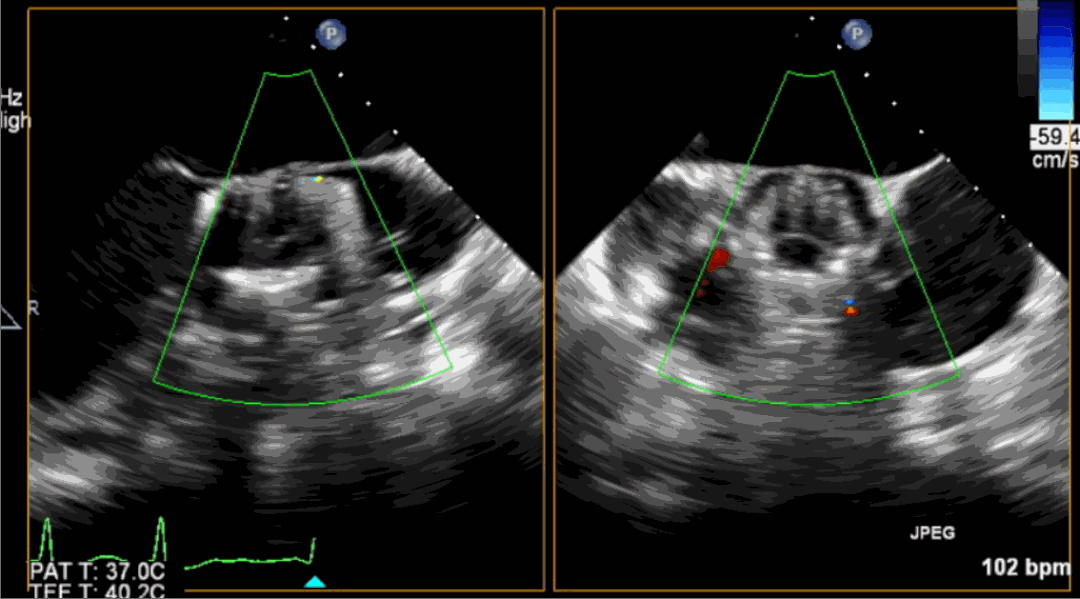

術(shù)后超聲影像圖

手術(shù)采用經(jīng)心尖入路,對(duì)患者進(jìn)行全麻后,在左側(cè)心尖處做3-4cm微創(chuàng)手術(shù)切口,在DSA及超聲引導(dǎo)下手術(shù)順利完成。從導(dǎo)入器械到完成瓣膜置入,僅耗時(shí)約10分鐘。術(shù)后即刻主動(dòng)脈瓣返流程度由術(shù)前大量返流轉(zhuǎn)為消失,患者于導(dǎo)管室拔除氣管插管,次日由ICU轉(zhuǎn)入普通病房。